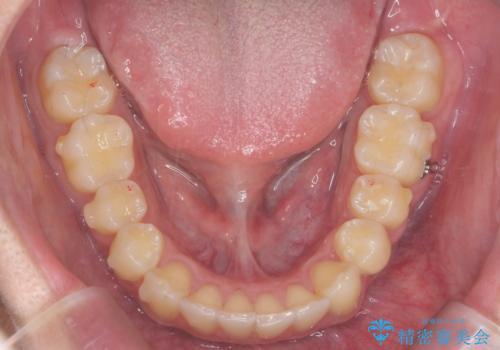

過蓋咬合・上顎前突・叢生を改善するマウスピース矯正

・前歯の深い噛み合わせ (過蓋咬合)

・上顎前突(Angle Class2)

・叢生(がたつき)

以上のような問題点をマウスピース矯正インビザラインとマイクロインプラントを用いて矯正治療を行い改善して行きます。

20時間以上のマウスピース装着、ゴムかけを遵守していただいたおかげでしっかりと噛み合わせ、がたつきの改善を行うことができました。